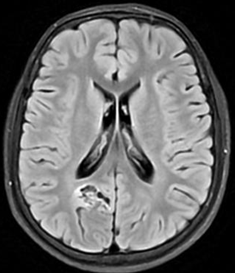

MRI study at admission revealed an ill-defined, irregular, heterogenous, nonenhancing, predominantly cortical-based bubbly appearing cystic lesion involving the right posterior parietal lobe with no perilesional edema – findings that were compatible with a diagnosis of DNET – Type 2 (Figure 1-7).1

Figure 2 Axial fluid-attenuated inversion recovery (FLAIR) MR images. Lesion appears hypointense with respect to normal white matter and isointense to intraventricular CSF, with some hyperintense internal septa. A well-defined hyperintense rim separating the tumor from the surrounding normal brain is visible (arrow). This is referred to as the FLAIR hyperintense ring sign.

Figure 4 Axial susceptibility-weighted MR image (MIP) obtained through the level of lesion. No abnormal vessels or abnormal signal intensity are seen, suggesting the absence of calcium or blood degradation products.